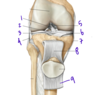

Which structure labels the anterior cruciate ligament?

Which structure labels the posterior cruciate ligament?

Anterior cruciate ligament = #2

Posterior cruciate libament = #1

Which structure is labeled by #10?

What is its function?

What are its attachments?

Tibialis posterior

Foot inversion, plantarflexion

Tibia, fibula, interosseous membrane + sole of the foot (tarsals)